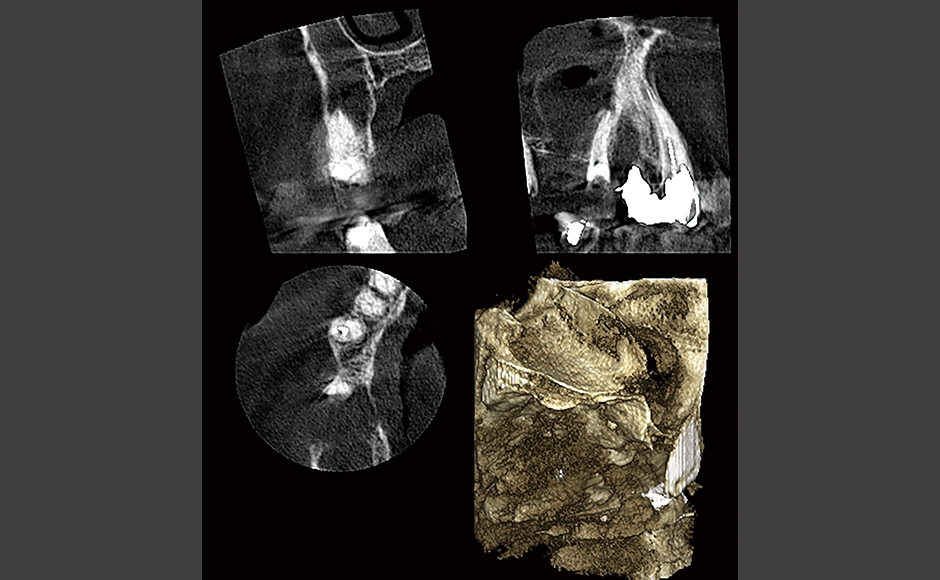

- レーザー症例1 他院より精査加療依頼

- レーザー症例2 左上奥歯が腫れて痛いとのことで急患来院。先週までは目の下まで腫れていたが、今は治ってきているとのこと。

- レーザー症例3 左上奥歯がズキズキ痛む。